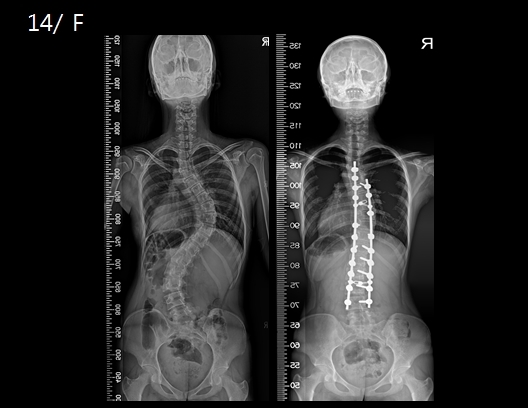

그림= 14세 여자 척추측만증 환자. 흉추와 요추 만곡이 모두 주만곡인 환자로 수술 전(왼쪽) 64도, 54도인 각도가 변형교정술 및 후방 기구 고정술 후(오른쪽) 18도, 14도로 교정됐다.